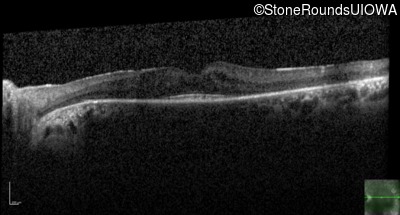

Optical Coherence Tomography - Right - 20/40

Exemplar / OCT Stack

OCT Stack